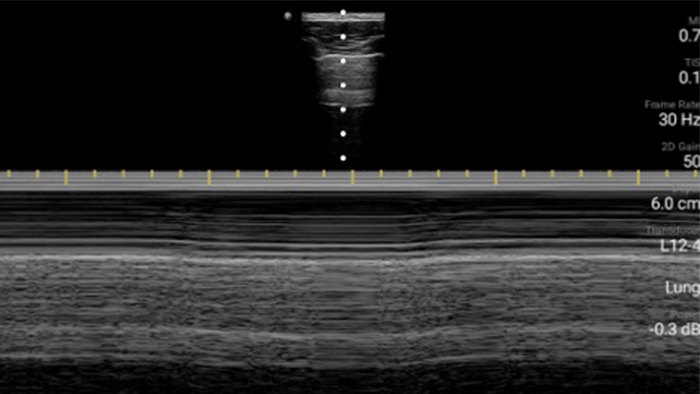

Use Lumify for airway and pulmonary assessment

Lumify POCUS solutions can help you detect the endotracheal tube within the trachea, assist in emergent cricothyrotomy procedures, diagnose pleural effusion and interstitial alveolar diseases.

Basics of lung ultrasound